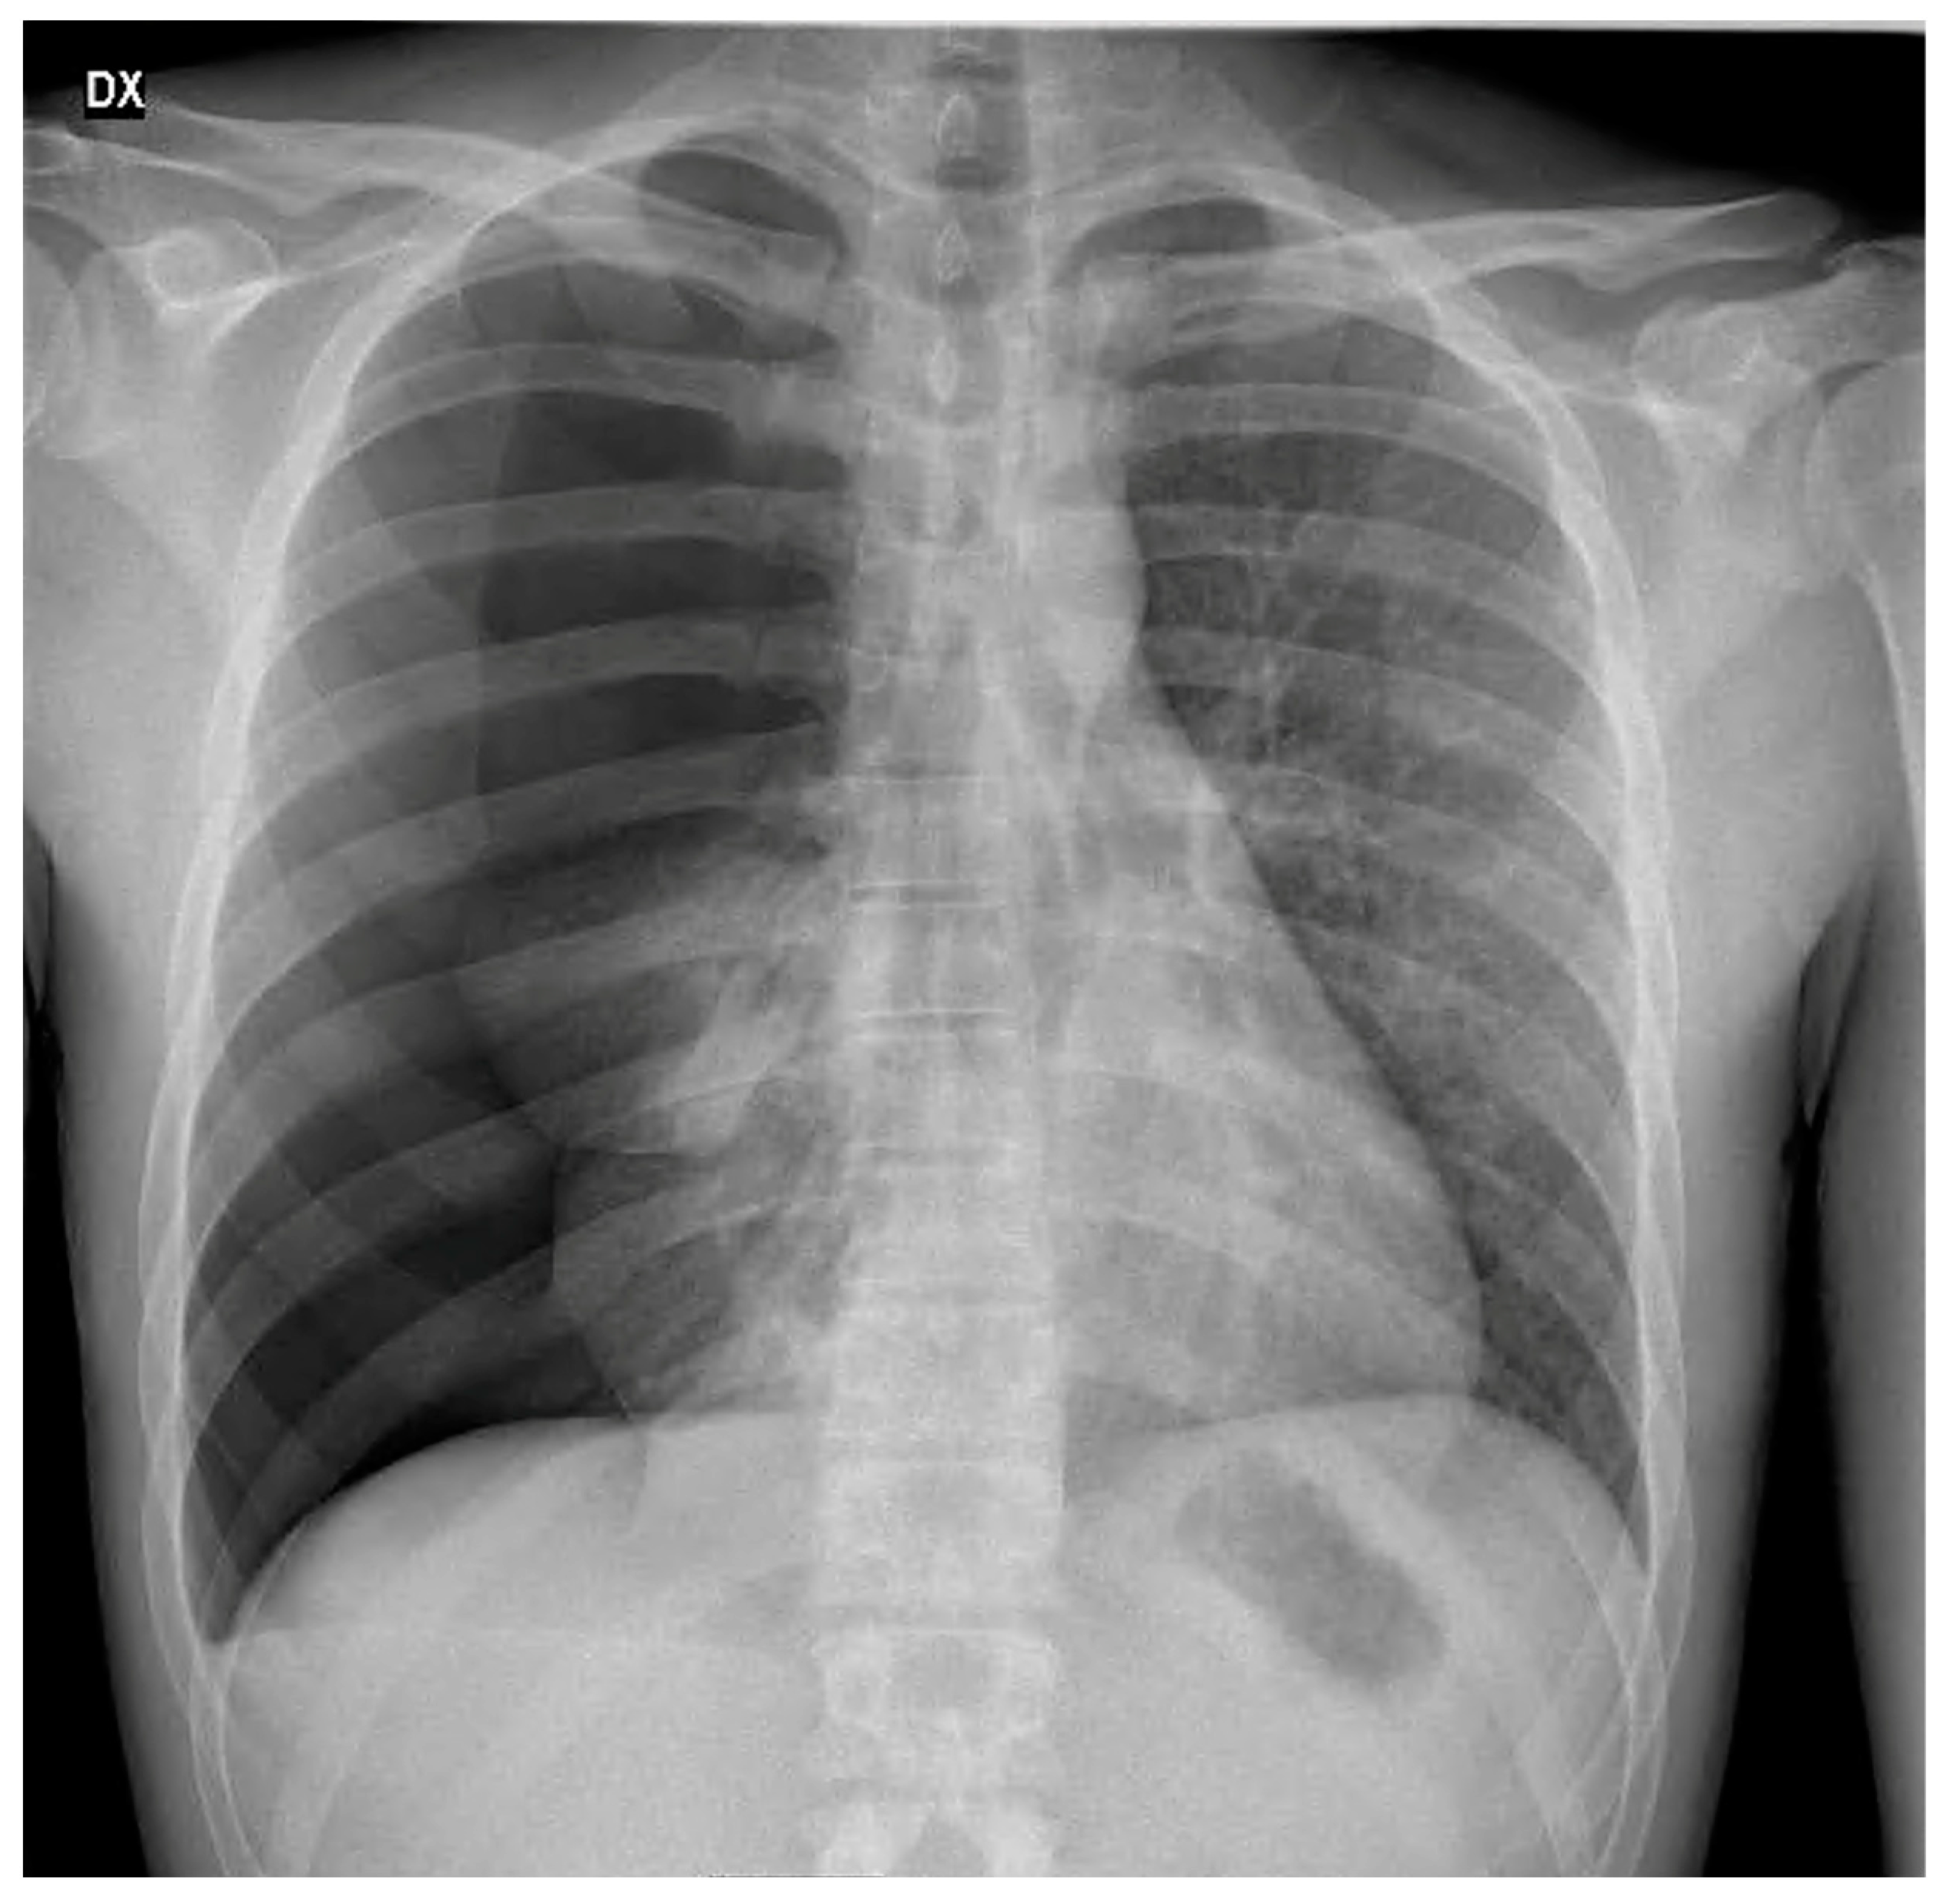

3.1. Case 1

3.2. Case 2

3.3. Case 3

4.3. Clinical and Radiological Features